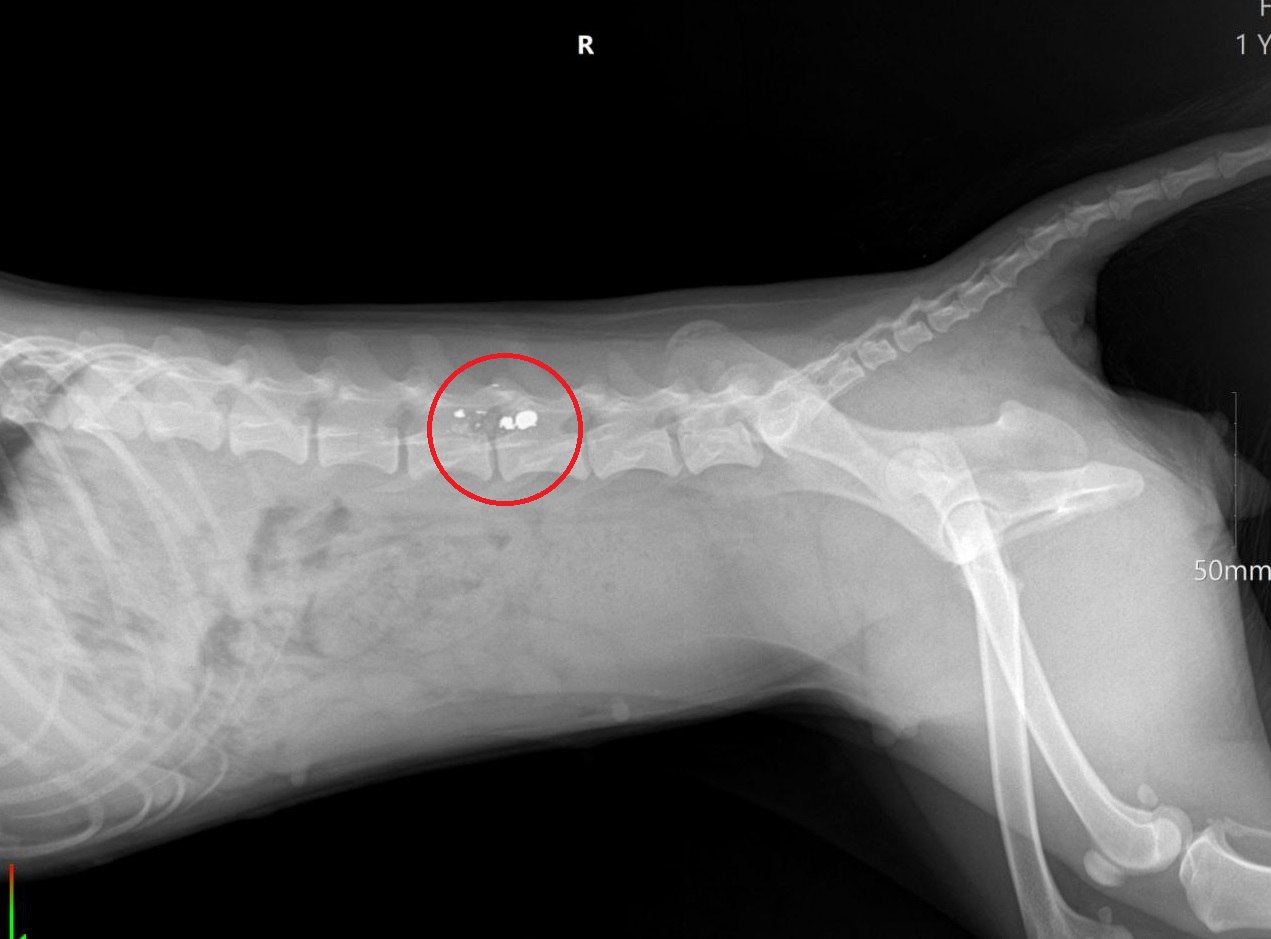

Все произошло в конце октября в селе Горнозаводском. Об этом полицейским сообщила 45-летняя хозяйка собаки. После выстрела женщина отвезла питомца в ветклинику, но, несмотря на помощь врачей, тазовые конечности животного теперь парализованы.